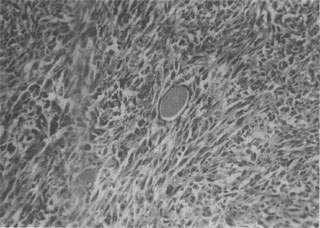

1.纤维肉(fibrosarcoma) 是肉中常见的一种,其发生部位与纤维相似,以四肢皮下组织为多见。分化好的纤维肉细胞多呈梭形,异型性小,与纤维有些相似;分化差的纤维肉则有明显的异型性(图7-17)。纤维肉分化好者生长慢,转移及复发较少见;分化差者生长快,易发生转移,切除后易复发。

图7-17 纤维肉

细胞呈梭形,体积较大,核大,核分裂像较多,具明显的异型性